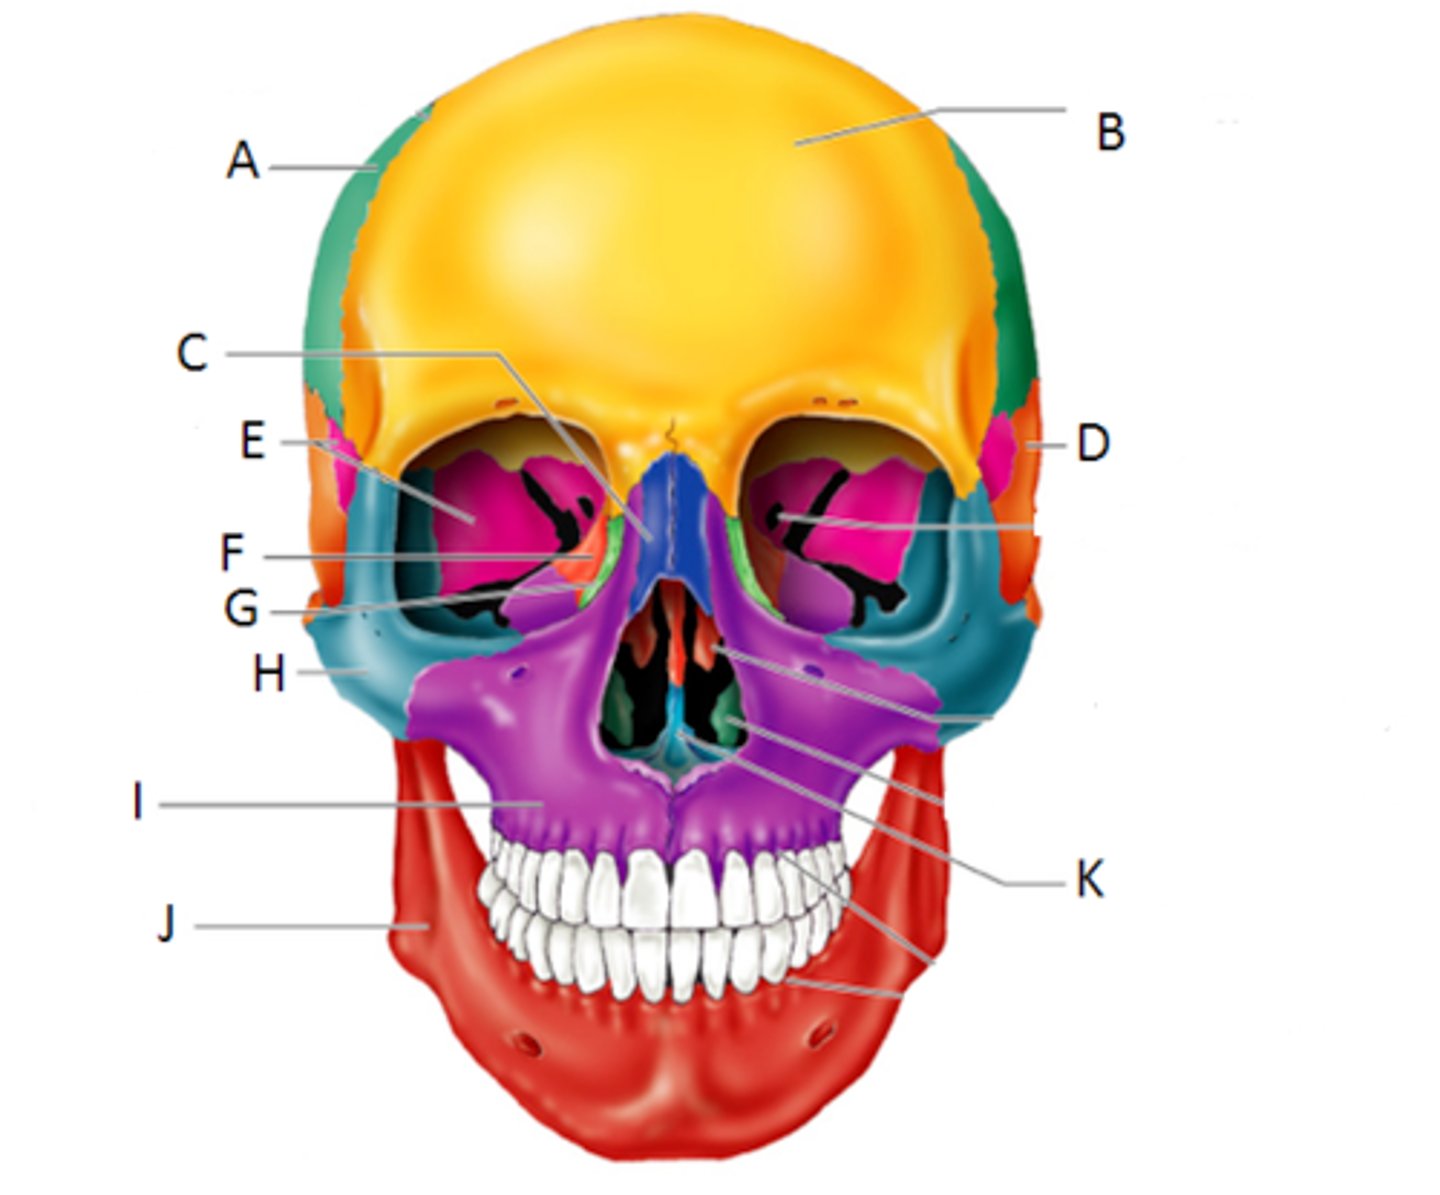

Skull

The skeleton of the head forming a bony case that encloses and protects the brain and chief sense organs and supports the jaws.

Mandible

The lower jaw, which causes the compressions during breastfeeding helping to milk the breast

Maxilla

Forms most of the upper jaw, and part of the hard palate, contains upper molars, premolars, and canines

Frontal Bone

the large cranial bone forming the front part of the cranium: the forehead and the upper part of the orbits

Temporal Bone

bone that forms parts of the side of the skull and floor of the cranial activity. There is a right and left temporal bone.

Occipital Bone

forms the posterior floor and walls of the cranium

Parietal Bone

either of two skull bones between the frontal and occipital bones and forming the top and sides of the cranium

Zygomatic Bone

cheekbone